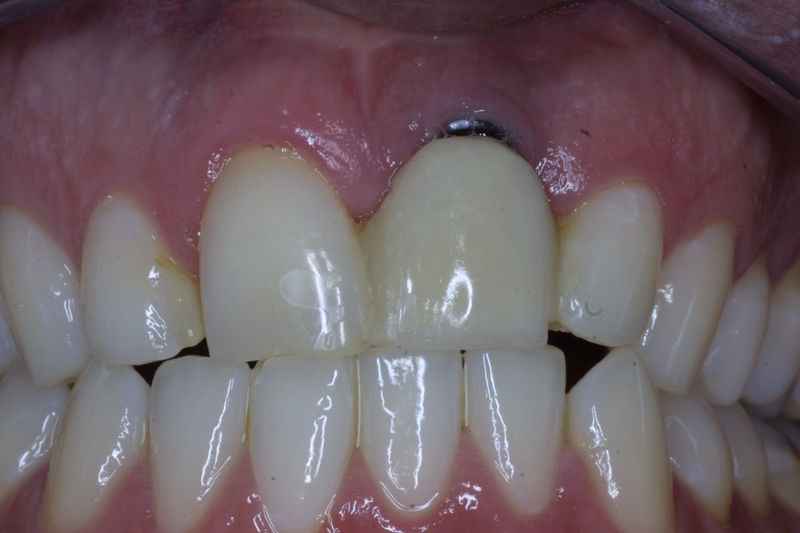

Los implantes dentales son pequeños tornillos de titanio u otro material biocompatible que se insertan en el hueso maxilar o mandibular para sustituir la raíz de un diente perdido. Actuando como un soporte sólido sobre el cual el dentista puede colocar un diente artificial (corona), un puente o una prótesis completa.

Son estructuras de titanio las cuales se colocan en el hueso y se utilizan para soportar coronas, prótesis fijas, removibles y totales. La colocación de los implantes se hacen previo análisis tomográfico.

Implante fracasado, extracción, carillas, coronas y prótesis fija.